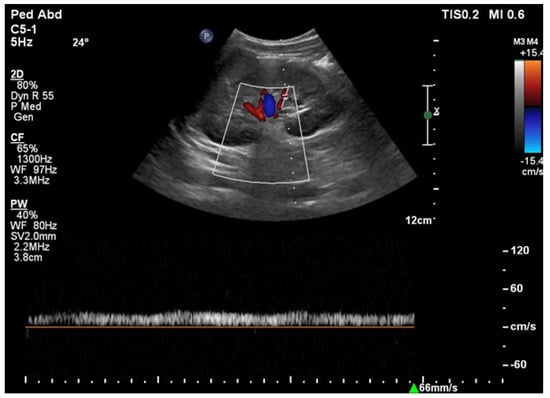

6.1. Ultrasound

- Drelich-Zbroja, A. Polish Society of Ultrasonography Standards—Update: Ultrasound Examination of Renal Arteries. J. Ultrason. 2014, 14, 297–305. [Google Scholar] [CrossRef]

- Stryczyński, Ł. Doppler ultrasound of renal arteries. Arter. Hypertens. Pract. 2022, 8, 186–199. [Google Scholar]

| Normal Value | Parameter |

|---|---|

| 100 cm/s * | PSV (peak systolic velocity) in artery trunk |

| 0.8–1.0 | RAR (renal aortic ratio) in artery trunk |

| ≤70 ms | AT (acceleration time) in intrarenal branches |

| 0.5–0.8 | RI (resistance index) in intrarenal branches |

| 0.78–1.33 | PI (pulsatility index) in intrarenal branches |

| >3 m/s2 | AI (acceleration index) in intrarenal branches |